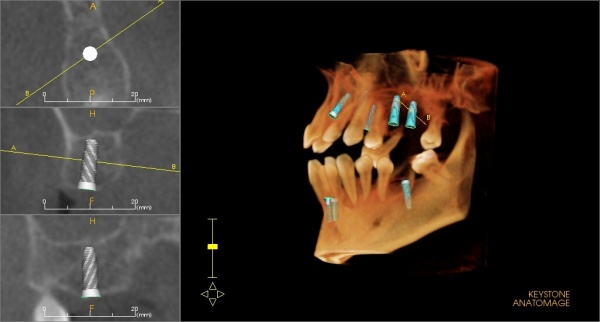

Trójwymiarowy model leczenia

W celu precyzyjnego zaplanowania zabiegu implantologicznego wykonujemy trójwymiarową (3D) wizualizację planowanego leczenia implantologicznego w programie DTX Studio Implant, polegającą na wirtualnym wszczepieniu implantów, a następnie stworzeniu precyzyjnego szablonu implantologicznego. Procedura ta pozwala na idealne umiejscowienie implantów, tak aby osiągnąć jak najlepszy efekt estetyczny i kliniczny. Planowanie 3D wykonywane jest w oparciu o badanie tomografii komputerowej CBCT, które jest wykonywane na miejscu w naszej Pracowni Tomografii Komputerowej CBCT.